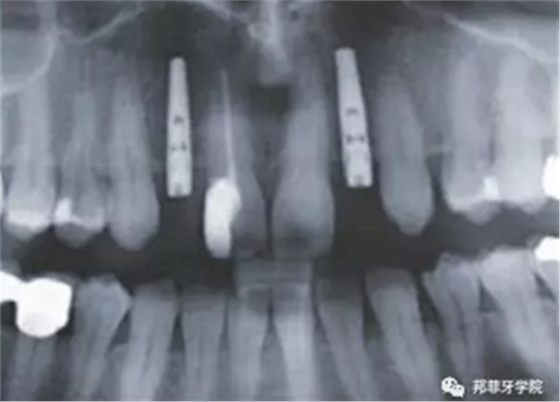

圖2:治療前全景片

牙齦成型器周圍應嚴密縫合,防止唾液進入切口(圖9)。X線片顯示植體位置理想(圖10)。愈合期未見并發(fā)癥,植體周圍牙齦愈合良好(圖11)。十周后取模,椅旁制備臨時牙(圖12),并制作螺絲固位PEEK基臺。

圖 10:拍片復查植體位置